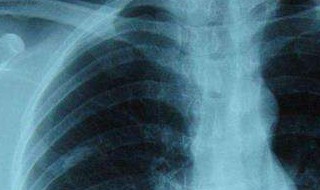

肺纤维钙化灶主要是因为患者曾经患有肺部疾病,例如肺炎、肺结核等,疾病痊愈后,在肺部所留下的未能完全吸收的疤痕,一般是不用担心的。患者可以按照医生的安排,定期做胸部检查,观察病灶的情况,随着时间推移,这种病灶可以吸收,或者长期存在,只要不影响患者正常的肺功能,是不需要特别治疗的。平时注意肺的养护,食用些具有清肺作用的食物。